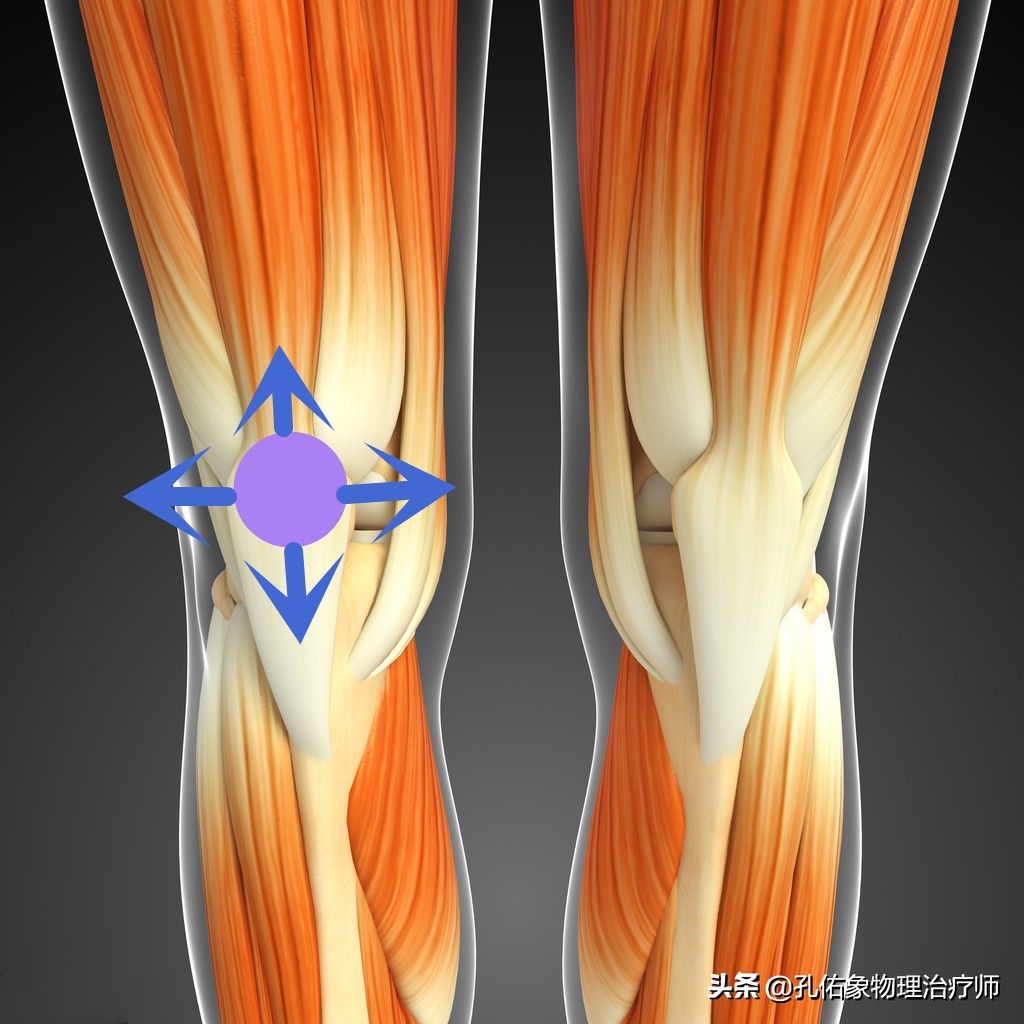

因为膝痛,会使稳定膝盖骨周围的韧带、肌肉打破原有的平衡;比方说现在很多人因不注意锻炼,常见于大腿外侧很紧,而膝盖骨内上缘处的股内侧斜肌就会很弱,从而影响到膝的受力,就会导致小腿发生旋转,最终使脚巴掌发生受力不均的情况下行走,毫无疑问就会出现足底疼痛。

比如说,常见的大腿内侧斜肌和内收肌的离心力量强化训练,臀大肌的离心强化训练;阔筋膜张肌和髂胫束的放松训练;膝关节的本体感知训练等等。